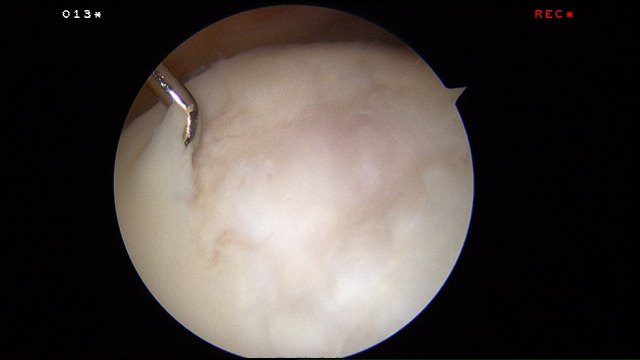

Microfracture surgery is an articular cartilage repair surgical technique that works by creating tiny fractures in the underlying bone.

The beauty of this surgery is that it is done through key-holes (using arthroscopy) and with easily available tools called chondral picks.

Arthroscopic enhanced microfracture was performed.